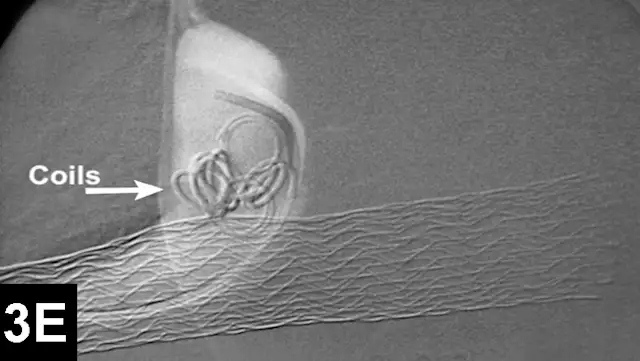

In IR, the goal for intrahepatic portosystemic shunts is to reduce the perioperative mortality rates associated with traditional open surgery and to improve outcomes (Figure 3). The author has recently reported 100 cases of intrahepatic portosystemic shunts in dogs that have been managed using IR techniques. Perioperative mortality rates were approximately 3%, and other complications were minor. The majority of these dogs have continued to do well following prolonged follow-up times.12

Figure 3A: Serial fluoroscopic images in a dog with a left divisional intrahepatic shunt.

The dog is in dorsal recumbency with the head to the left.

Double venogram of caudal vena cava (CVC) and portosystemic shunt (PSS) demonstrating entrance of shunt (*) into CVC.